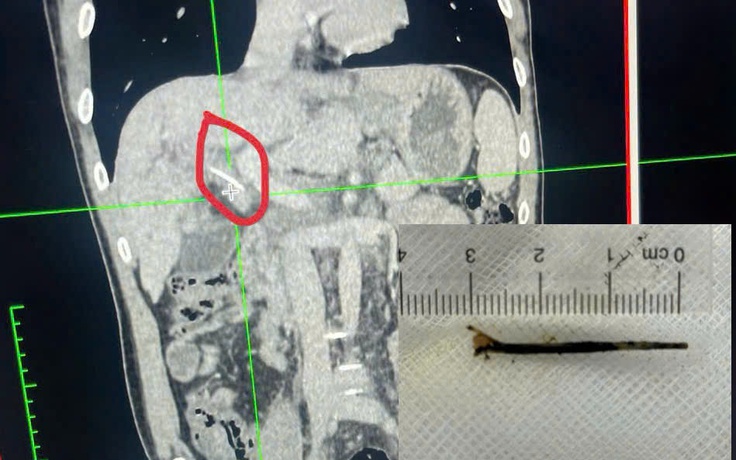

Hóc xương cá dài 3 cm xuyên vào đường mật... tưởng bị ung thư

Bệnh nhân 45 tuổi bị đau bụng hạ sườn phải kéo dài, kèm vàng da, vàng mắt, nghi ngờ bị ung thư… vào viện bất ngờ phát hiện bị hóc xương cá dài 3 cm xuyên qua thành dạ dày vào đường mật.